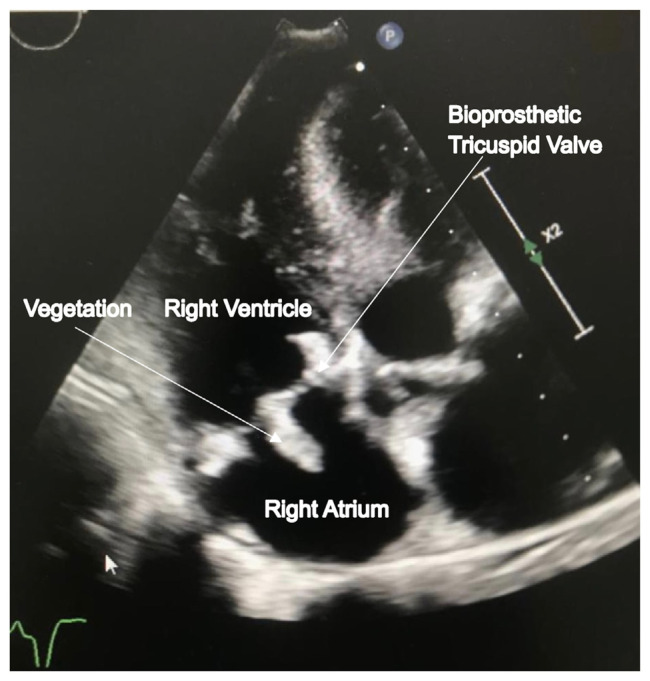

Fungal endocarditis (FE) is a rare yet life-threatening condition, especially in hemodialysis (HD) patients with indwelling long-term catheters. Symptoms often overlap with non-fungal infective endocarditis, making diagnosis difficult. As FE incidence increases, healthcare providers face challenges in diagnosing and managing this severe condition. Early suspicion of FE is crucial for patients with long-term catheters. We reported a 23-year-old male with end-stage renal disease (ESRD) on HD that developed FE affecting the tricuspid valve, requiring valve replacement and anti-fungal medication. Despite these interventions, he had recurrent Candida prosthetic endocarditis (CPE). Currently, he is receiving anti-fungal medication, with plans for a third surgery.